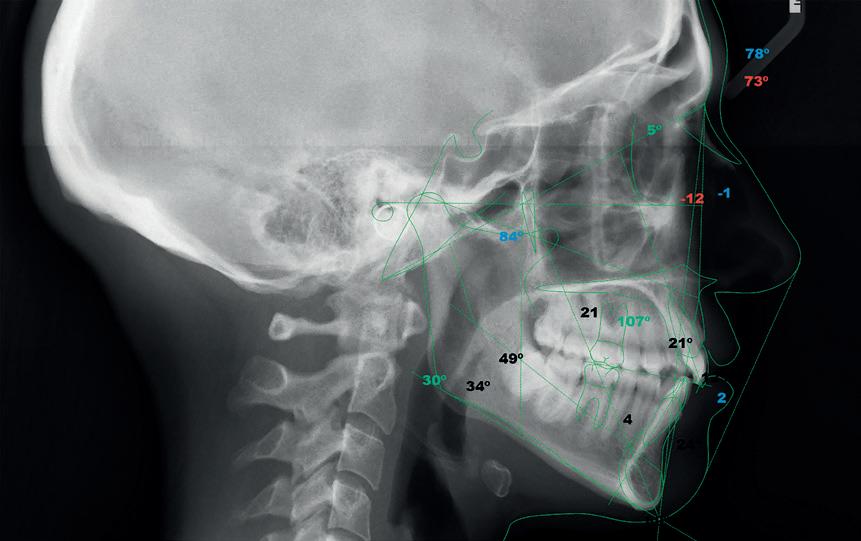

Fig. 2. Cefalometria digital.

Os constantes avanços tecnológicos exercem uma enorme influência no indivíduo e na sociedade, não só nos aspetos mais básicos da vida quotidiana, mas também em áreas nobres como a medicina, economia, educação e comunicação, tornando-se uma ferramenta de trabalho inestimável. Dentro da Medicina Dentária, a ortodontia não é exceção. Desde 1982, que programas cefalométricos computorizados têm vindo a ser desenvolvidos e melhorados, para a realização não só de planos de tratamento de correção e alinhamento mas também de cooperação com a cirurgia maxilofacial.

Durante anos, os traçados cefalométricos foram a única tecnologia digital usada em ortodontia. Em 2003, foram introduzidos no mercado, os tratamentos ortodônticos virtuais usados para a confeção de aparelhos fixos e alinhadores transparentes, tendo sido a Align Technology™ pioneira com o produto Invisalign™.